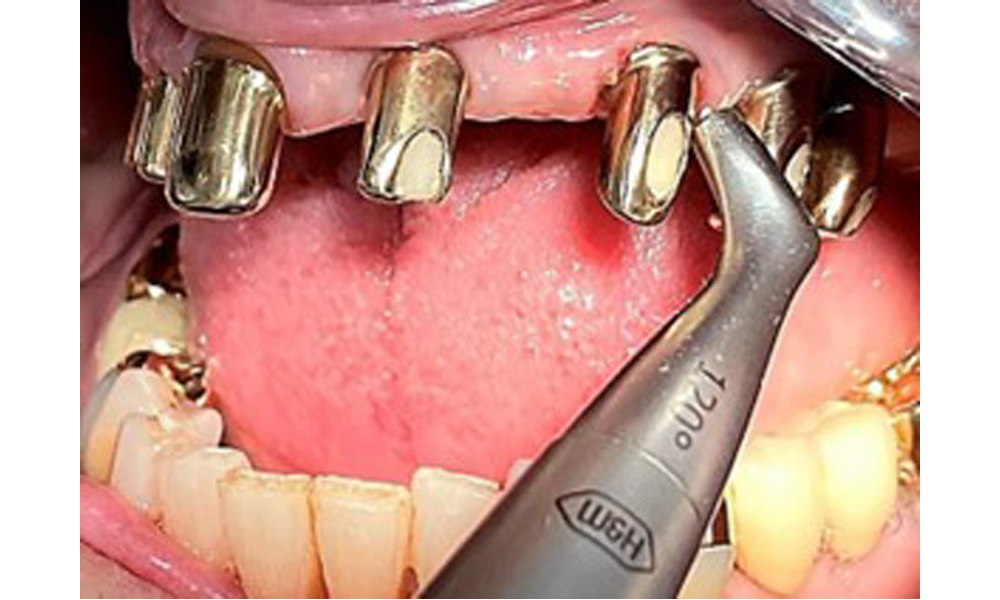

Bearbeitung der Implantatoberfläche mit Handinstrumenten aus Titan.

Abb. 10: Bearbeitung der Implantatoberfläche mit Handinstrumenten aus Titan.

Darstellung einer Peek-Ultraschallspitze (hier Proxeo Ultra, Firma W&H) zur Bearbeitung von Implantatoberflächen bei mineralisierten Belägen (mineralisierte Beläge sind im vorliegenden Fall nicht vorhanden, schematische Darstellung).

Abb. 11: Darstellung einer Peek-Ultraschallspitze (hier Proxeo Ultra, Firma W&H) zur Bearbeitung von Implantatoberflächen bei mineralisierten Belägen (mineralisierte Beläge sind im vorliegenden Fall nicht vorhanden, schematische Darstellung).

Für die Entfernung von Zahnstein und Konkrementen am natürlichen Zahn kann Schall Ultraschall verwendet werden sowie konventionelle Handinstrumente (8). An den Implantaten sind für mineralisierte Beläge Titan- oder Kunststoffküretten (Abb. 10) einzusetzen oder ein Kunststoff- bzw. Peek-Ansatz (Abb. 11) für die Ultraschallbehandlung, um die Implantatoberfläche nicht zu beschädigen.